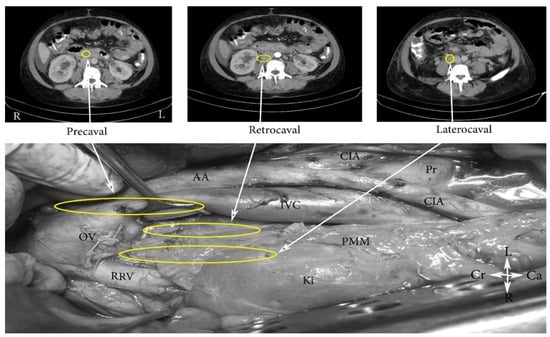

- The high paraaortic (supramesenteric) region is limited: ventrally—LRV; medially—AA; laterally—ureter and Gerota fascia; dorsally—IMA; caudally—psoas major muscle.

- The low paraaortic (inframesenteric) region is limited: ventrally by the IMA; medially—by the AA, dorsally—the left common iliac artery (CIA); laterally—the ureter and the Gerota fascia, caudally—the psoas major muscle.

- The paracaval region (includes laterocaval and retrocaval PALNs) is limited: ventrally—right renal vein (RRV); dorsally—midpoint of the lateral aspect of right CIA, laterally—right ureter and right psoas major muscle, caudally—the psoas major muscle.